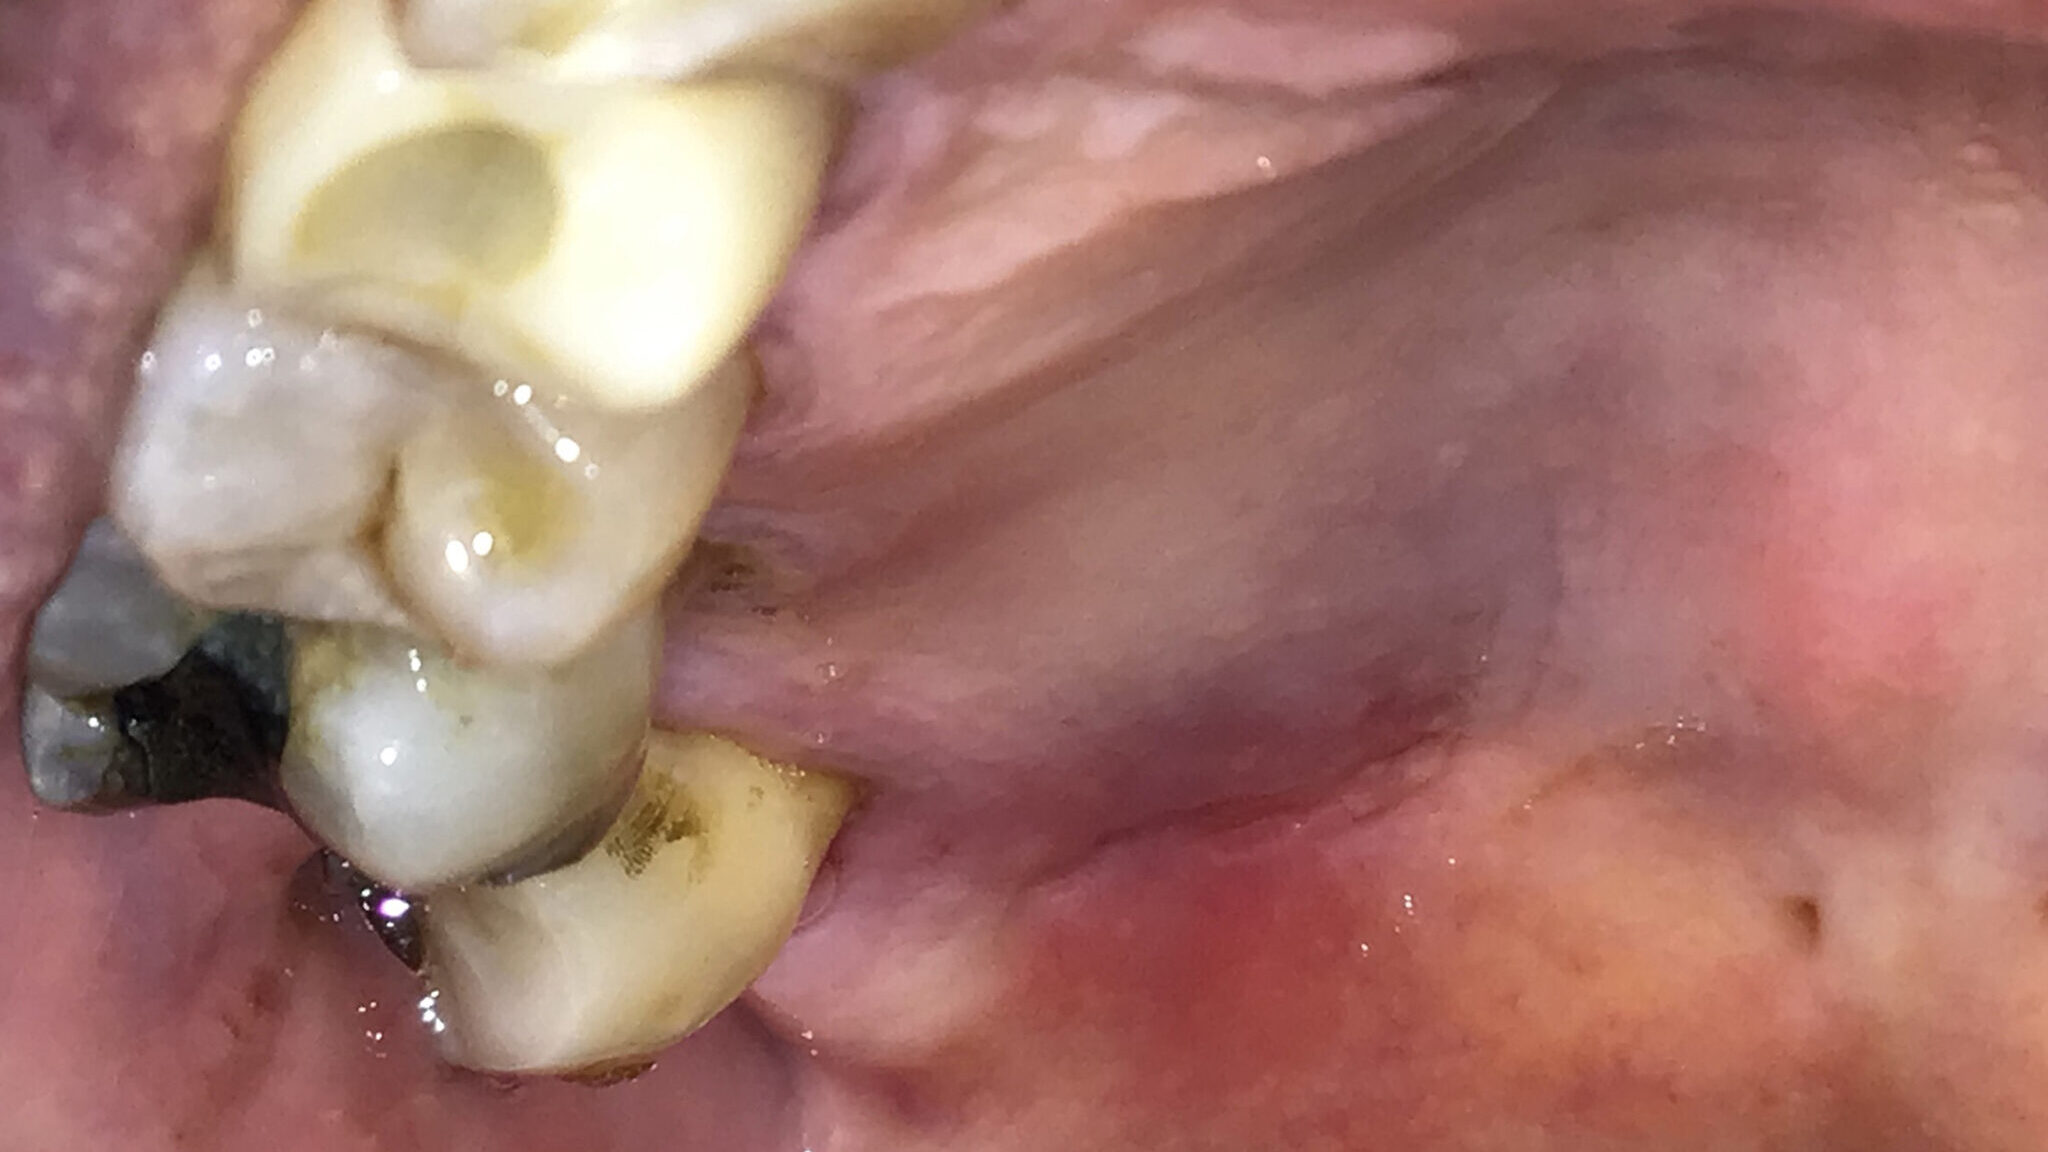

The Use of Artificial Intelligence in Third Molar Surgery Risk Assessment

Abstract Third molar removal complication rates can be as high as 30%. Risk assessment tools may lower these rates. Artificial intelligence (AI) driven prediction models are a promising approach to predict possible unfavorable outcomes and cone-beam computed tomography imaging may play an important role. AI prediction models are showing excellent results in research settings. To … Read more